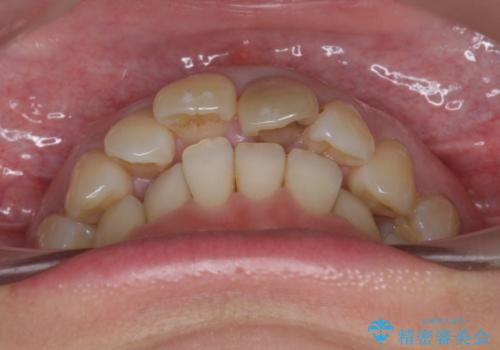

変色した前歯をセラミックでひっこめたい

- 前歯の色と、前突感を気にして来院。

全体的な矯正治療をすすめましたが、ご希望されませんでした。

左上の前歯の神経が失活(死んでいた)していたため、神経の治療を行いました。

また、右上の前歯を下げるため、便宜的に神経を取る治療を行いました。

結果、気になっていた色と角度が良くなり、大変喜んでいただけました。

右上1はひっこめた量が大きかったため、反対側の1番と切端をそろえるのに、多少長さは長くなりました。

右上2、左上2の補綴も提案はしましたが、最小限の本数で行っていくことになり、右上2の捻転(歯のねじれ)はそのままとなっております。